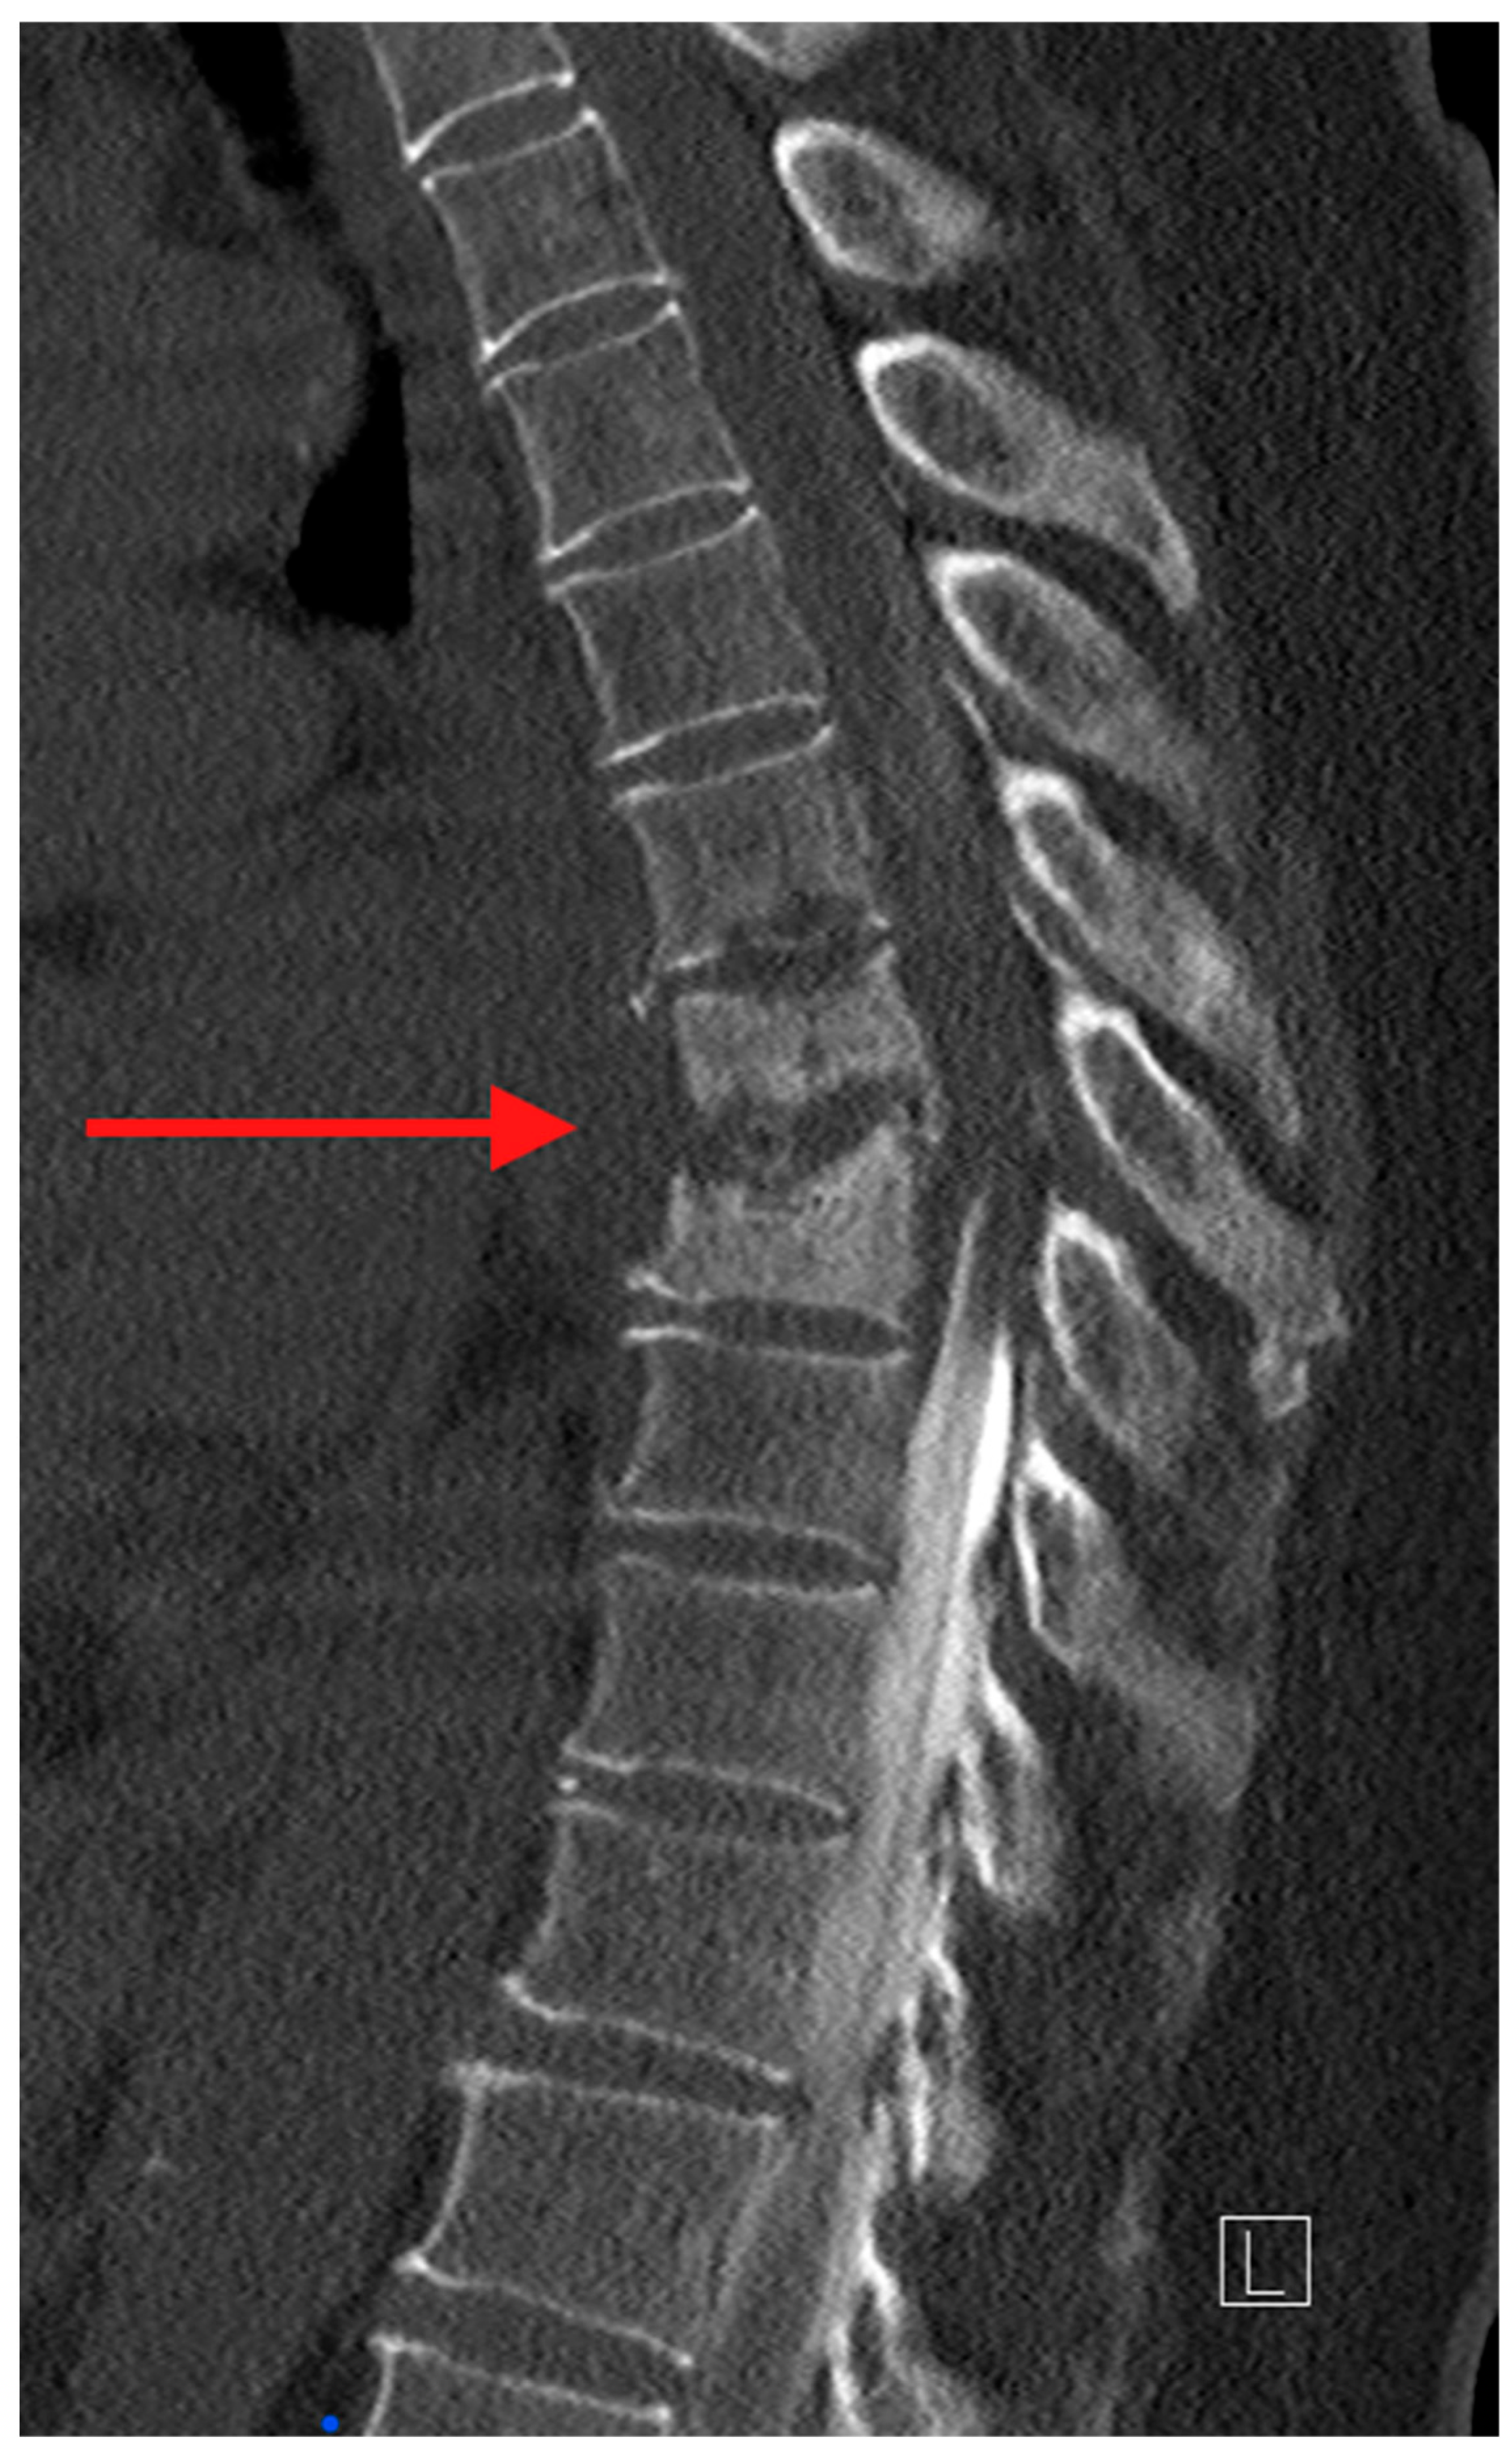

Computed tomography (CT) is the ideal imaging study to evaluate bony detail. CT allows for an accurate assessment of bony destruction, identifying subtle pathological fractures and assisting in evaluating spinal stability/instability (Figure 2). In the case where surgery is being considered, the ability to obtain 3-dimensional image reconstruction makes CT critical for surgical planning.

Figure 2. Sagittal CT myelogram of the thoracic spine. The red arrow is pointing to the destructive changes of several vertebral bodies in the mid-thoracic spine. Also noted is the myelogram dye in the spinal canal. It was injected caudal to cranial and the abrupt disappearance of the column of dye at the infected level suggests high-grade cord compression [4].